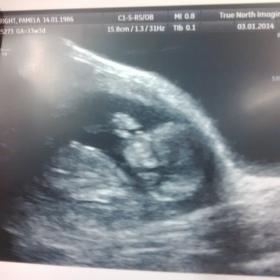

Sorry no clues....but how cute is the bottom pic of bub sucking his/her thumb!! Adorable!

^^Agree. That thumb pic is perfect. Such a cute bub. But sorry on the lack of a nub.